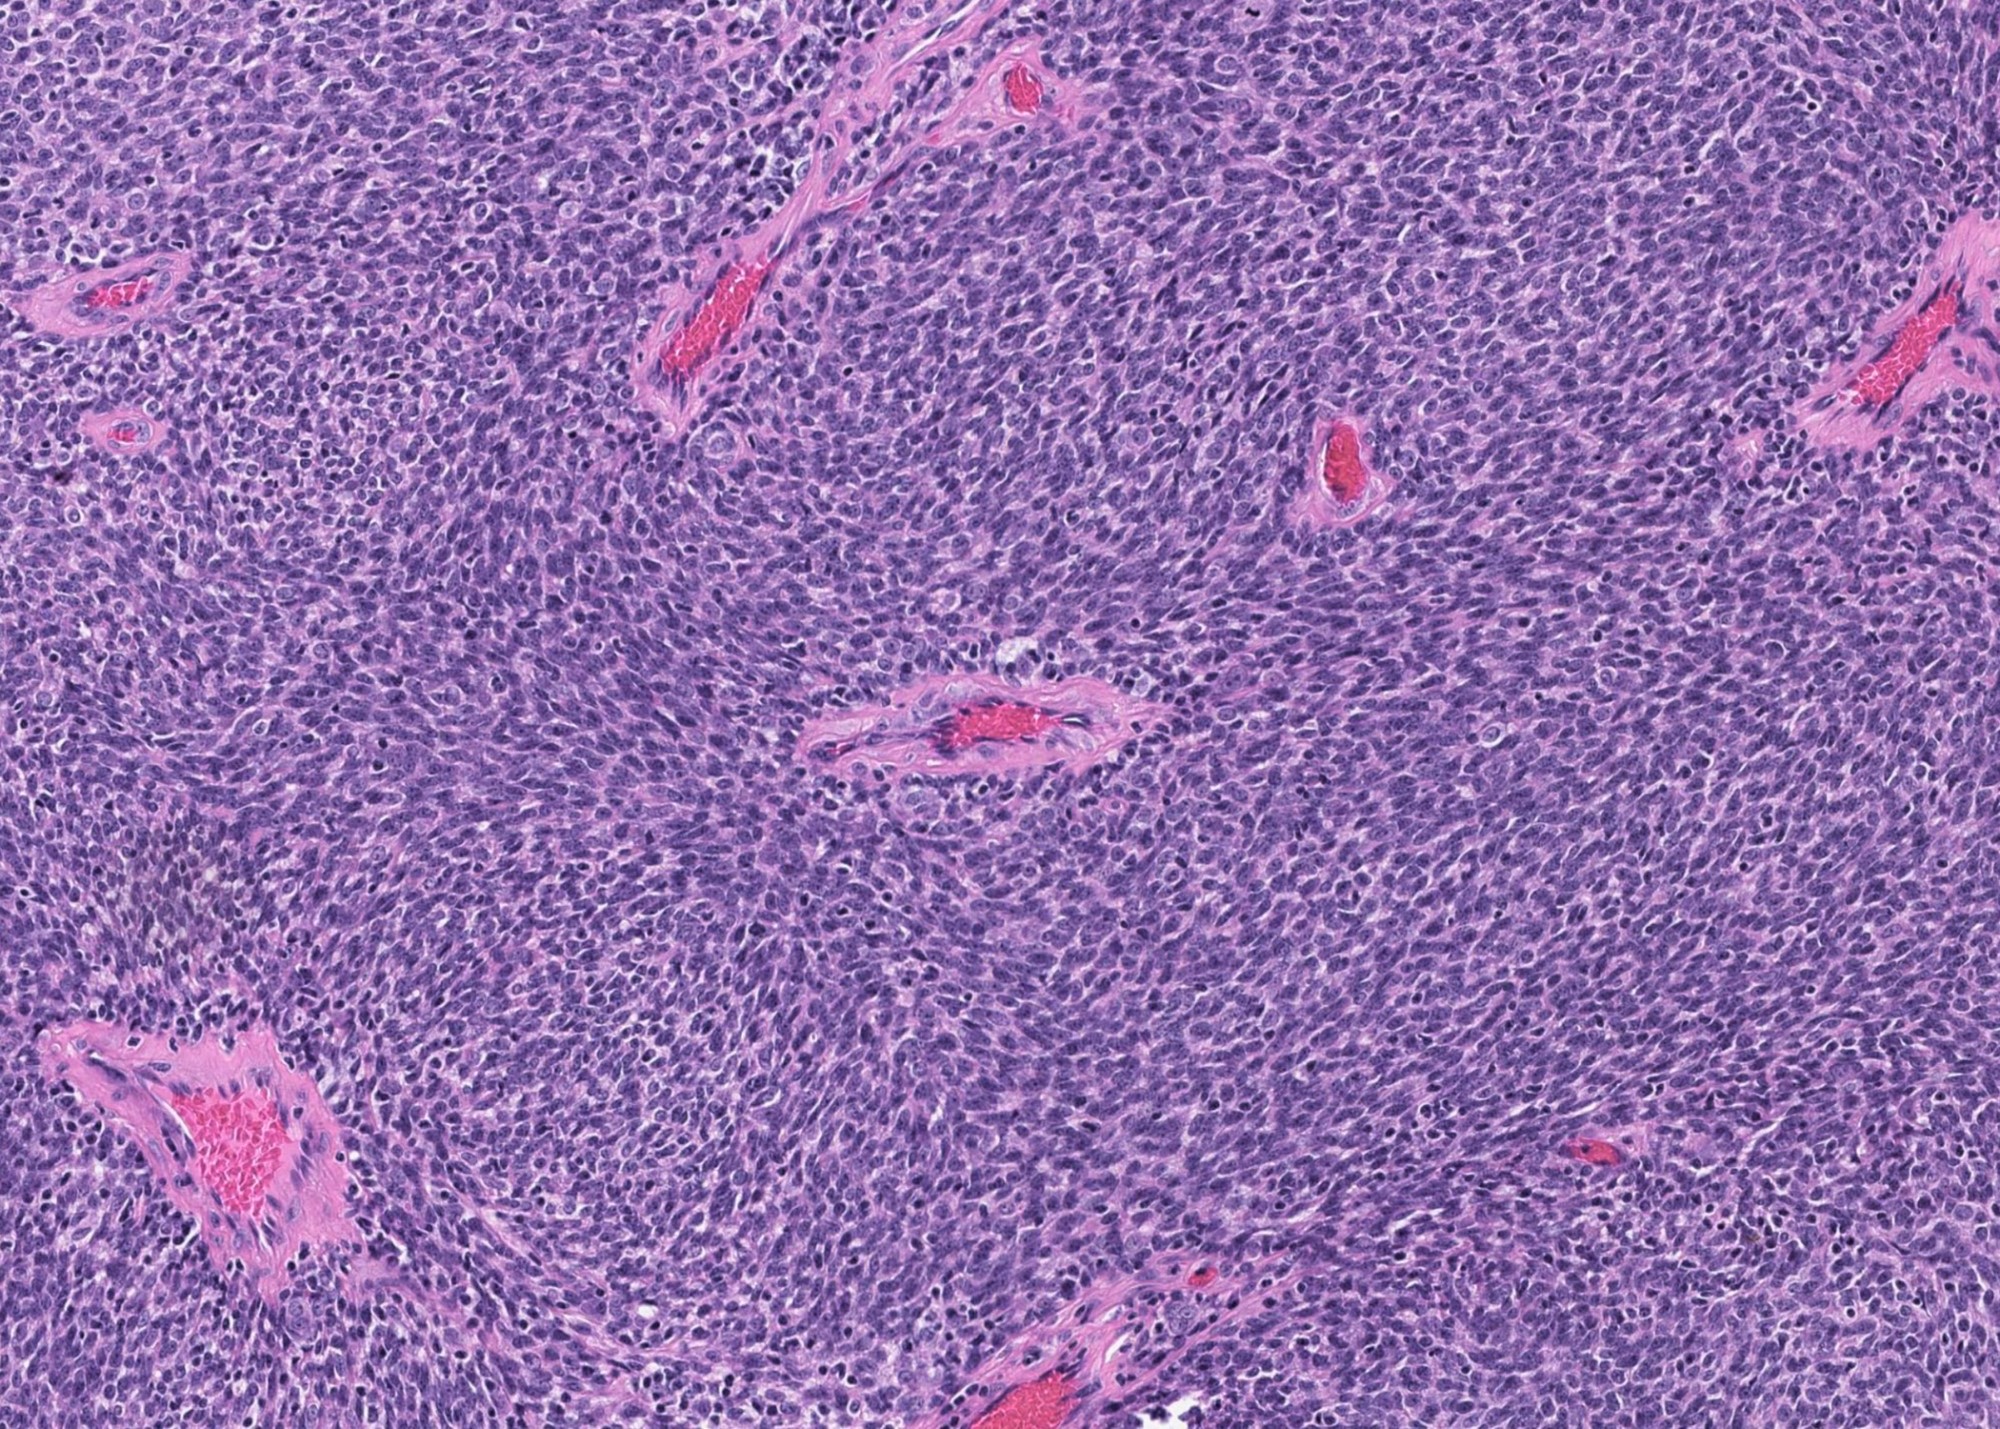

Microscopic (histologic) description

- Invasiveness is typically demonstrated as expansile invasive multinodular growth: myoepithelial carcinoma rarely shows infiltration of single cells / small clusters or desmoplastic reaction

- Nodules often have a hypocellular center with hyalinized stroma or bland necrosis surrounded by a hypercellular peripheral zone

- Tumor necrosis can be seen within the hypercellular central zone of a tumor nodule

- Currently, there is no well defined, widely accepted grading system: presence of tumor necrosis is considered by some as a feature of high grade myoepithelial carcinoma (Am J Surg Pathol 2015;39:931)

- Composed (near) entirely of myoepithelial cells showing various cytologic features, including clear cell, epithelioid, plasmacytoid or spindle cell morphology

- Hyalinized, myxoid or myxochondroid stroma may be seen in myoepithelial carcinoma de novo and ex PA

- Common architectural patterns include solid, trabeculae, cords, nests and single cells

- Presence of pre-existing / residual pleomorphic adenoma component can be seen in myoepithelial carcinoma ex PA

Microscopic (histologic) images

Contributed by Abeer Salama, M.D. and Bin Xu, M.D., Ph.D.

B. The low power H&E clearly shows invasion, which supports a diagnosis of carcinoma and excludes benign entities, such as pleomorphic adenoma. At high power, the tumor contains one type of tumor cells, which exclude all carcinoma with biphasic patterns (e.g. adenoid cystic carcinoma). The immunohistochemical profile is consistent with myoepithelial phenotype. Therefore, the correct diagnosis is myoepithelial carcinoma.